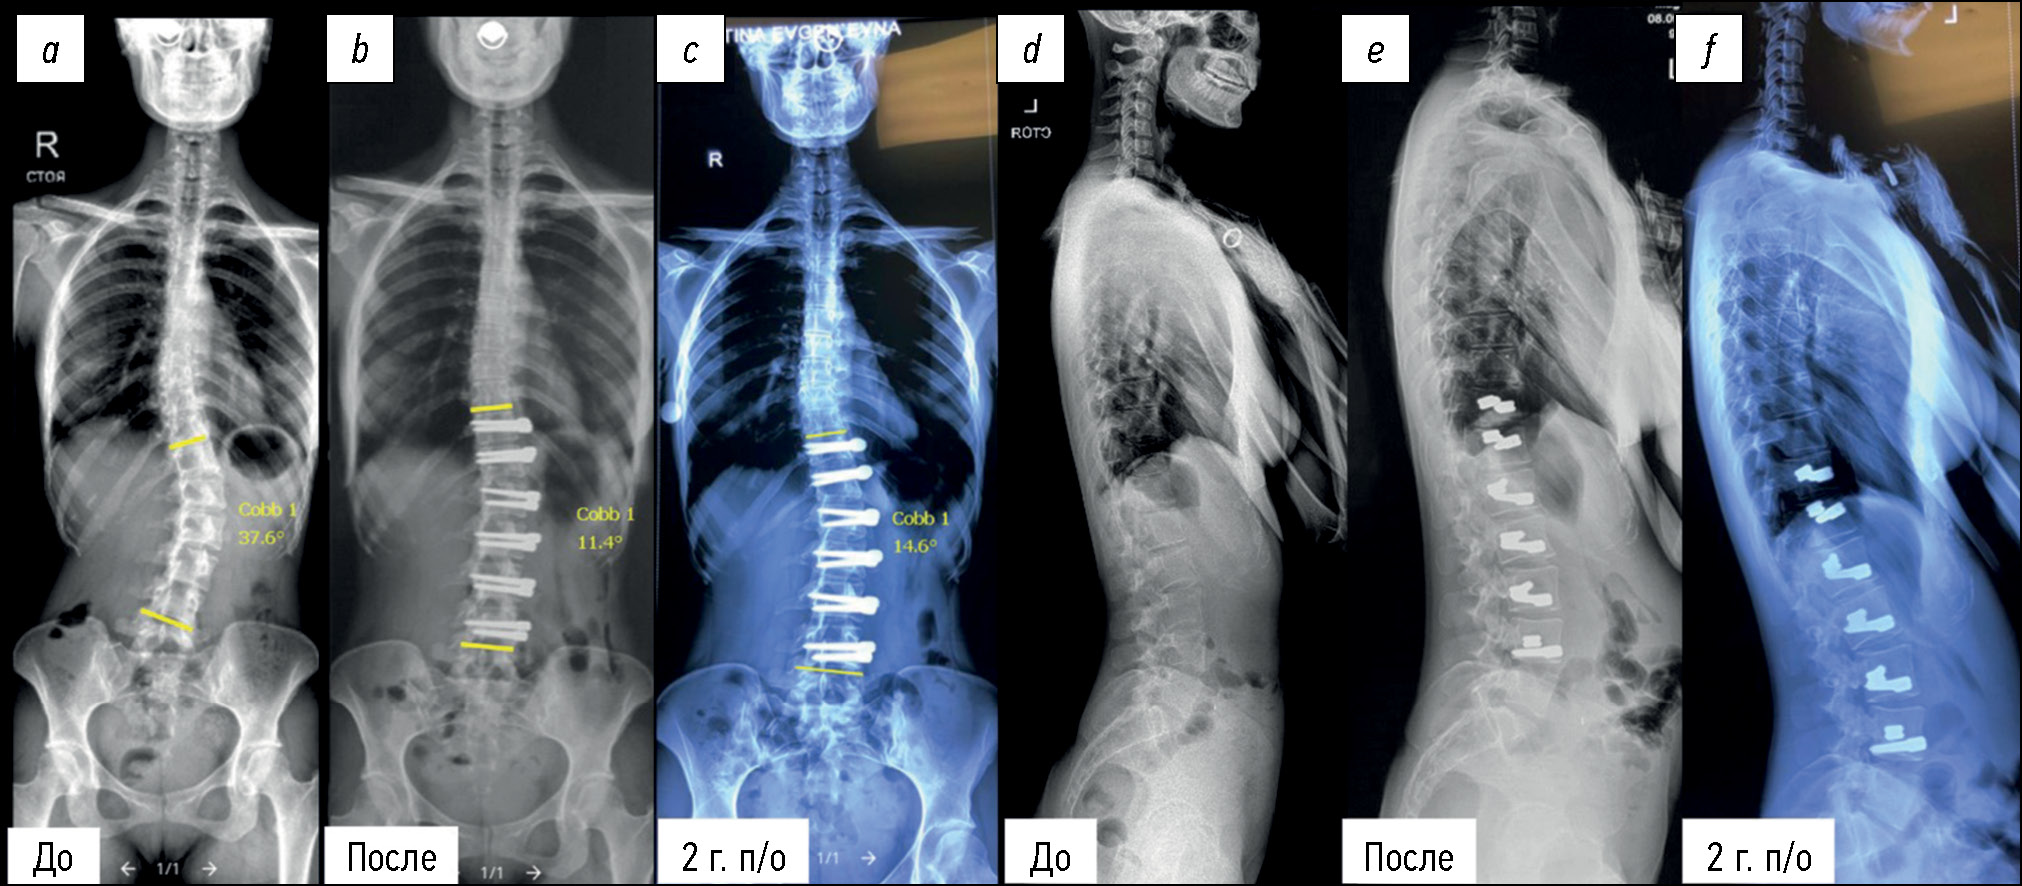

The mean Cobb angles in the thoracic ASC group at the first postoperative study and the last followup were 27.9°±5.3° and 25.2°±6.9°, respectively, compared with the preoperative value of 62.4°±10.9° (p <0.05). Patients who underwent surgery for lumbar/thoracolumbar scoliosis also demonstrated no significant loss of correction. The mean Cobb angles were 52.5°±8.4° preoperatively, 24.2°±12.4° postoperatively, and 27.2°±11.6° at the last followup (p <0.05).

The best results were achieved with both thoracic and lumbar/thoracolumbar correction (Fig. 2).

Fig. 2. X-ray of the patient before surgery (a, d), immediately after lumbar spine anterior dynamic scoliosis correction (b, e) and at the follow-up stage 2 years postop (c, f). There is no significant loss of correction.

The patients demonstrated a significant improvement in all preoperative Cobb angles immediately after the intervention. The correction was maintained in the majority of patients at followup, with a slight loss of correction observed in two patients.